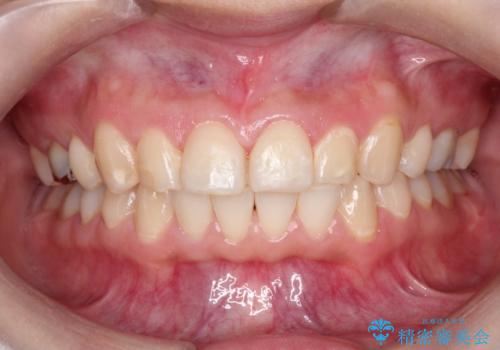

見た目だけではなくかみ合わせも良くなったと満足して頂きました。

治療後は見た目だけでなく、噛みやすくなったと満足していただけました。